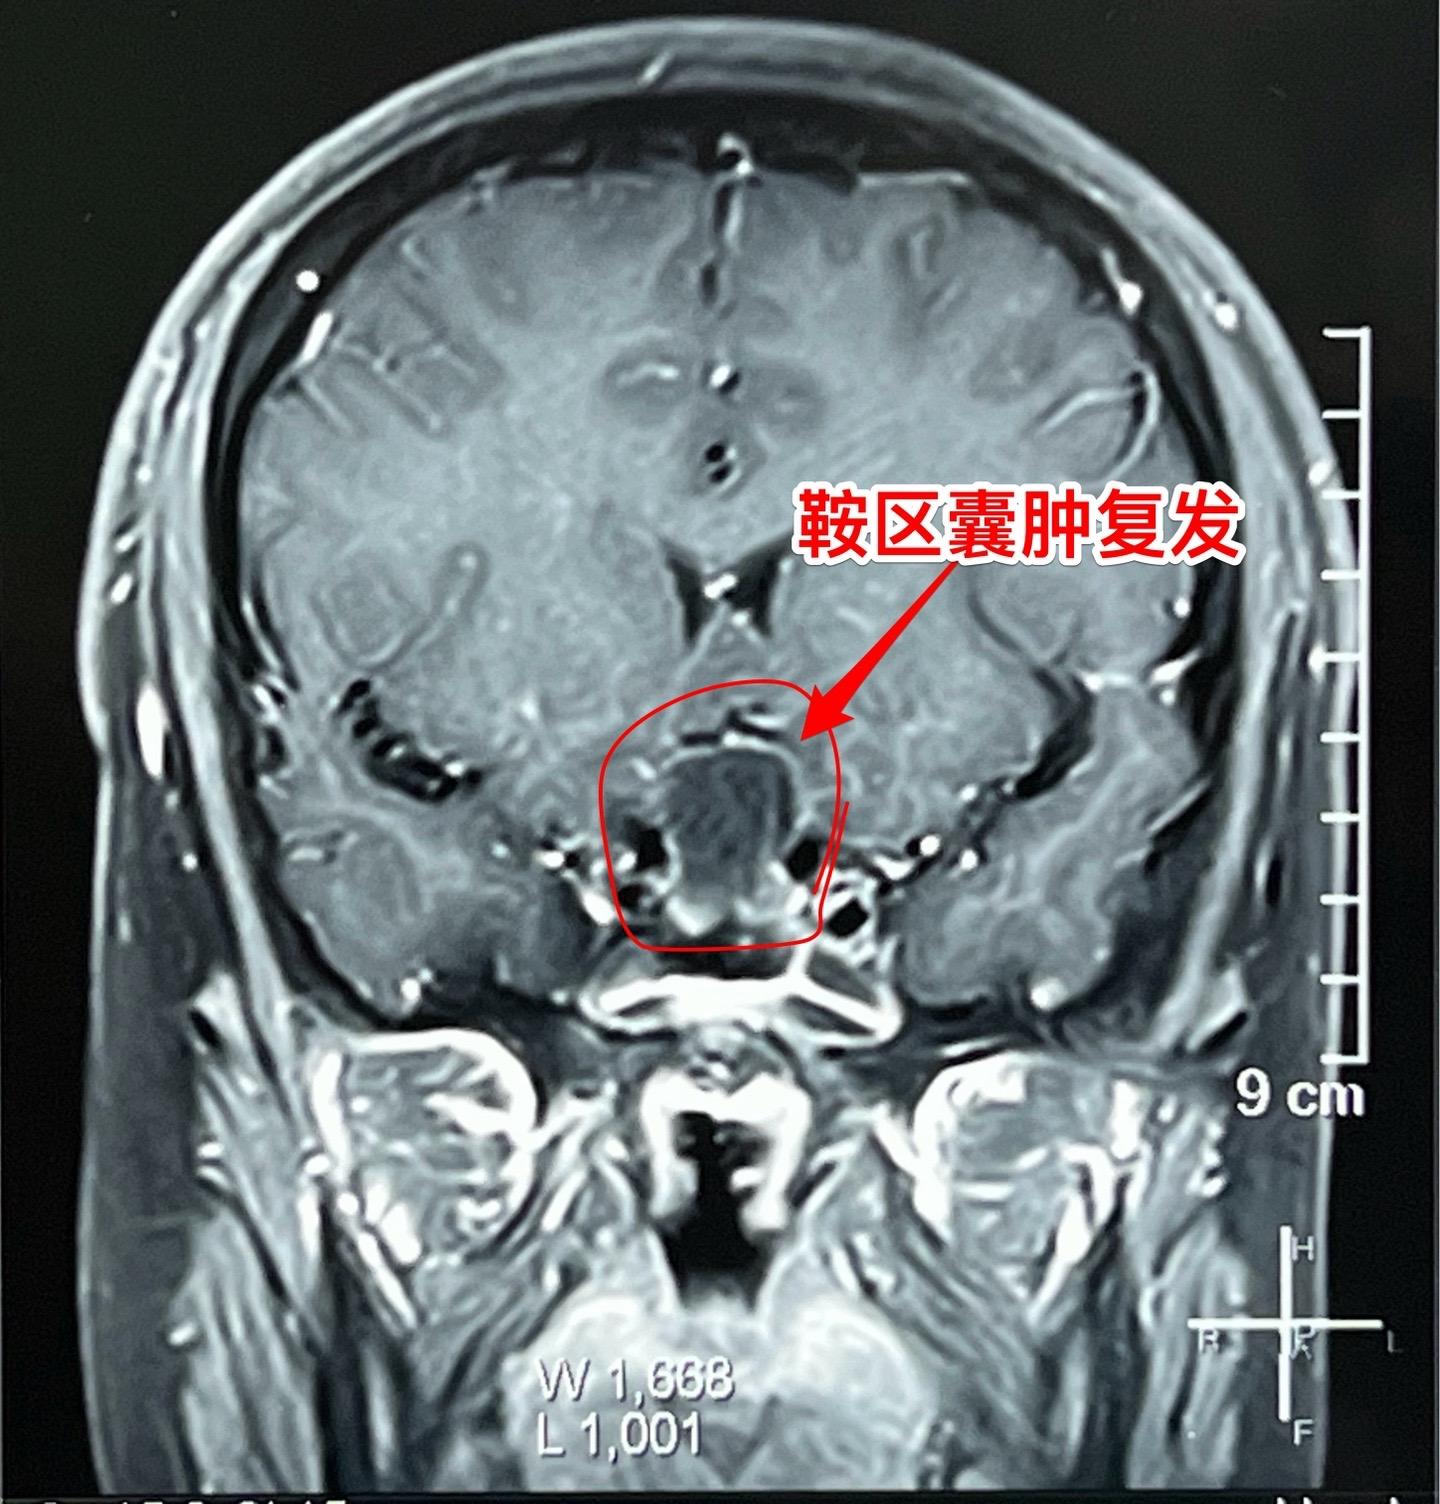

鞍区囊肿不能说是小问题(确诊拉克氏囊肿)16岁的男孩子2年前就因多饮多尿症状到医院检查发现鞍区囊肿,怀疑是拉克氏囊肿。这个病不是真性肿瘤,但是也不是小问题,也会导致尿崩症、生长发育迟缓、视力下降等问题。 他们一家选择了一个著名的医院去作手术,采用经鼻手术方式。遗憾的是手术中取得的标本最终未得出确切的病理诊断。手术后小孩子还出现了脑脊液鼻漏、颅内感染,受老罪了。 随后两年多时间内多次复查磁共振显示囊肿复发了,而且出现视力下降。然而小孩子对于第一次手术的痛苦印象太深了,故而拒绝作第